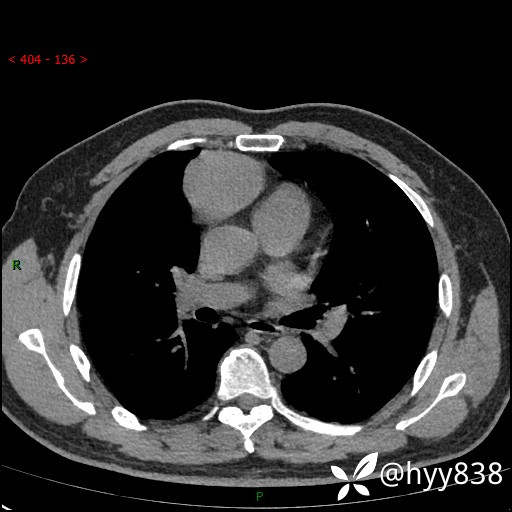

动脉期+静脉期

各期CT值